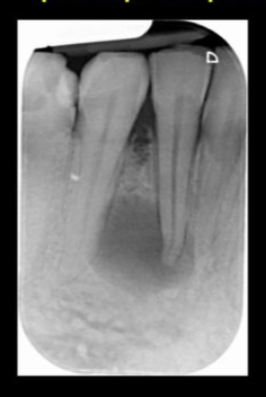

is the following periapical pathology or not?

yes

83

yes - root filled - PDL isnt continuous - lamina dura isnt continuous

84

no

85

86

yes - it is crowned - apical radiolucency - lamina dura tracking off

87

cant tell

88

89

yes - lamina dura tracking off

90

no PDL widened probs cus of brace

91